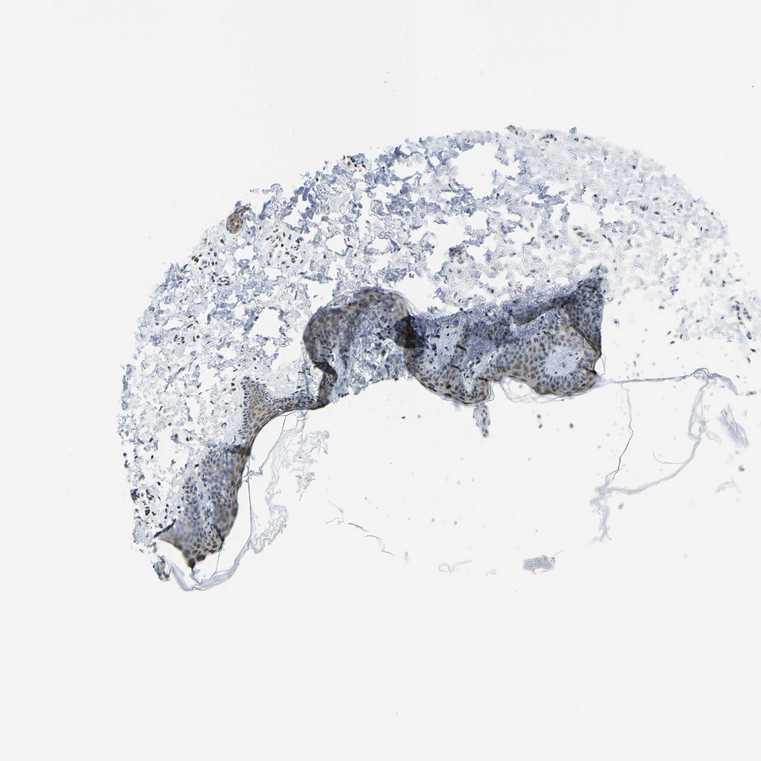

SKIN 2 - Antibody stainingi

Antibody staining in the annotated cell types in the current human tissue is reported as not detected, low, medium, or high, based on conventional immunohistochemistry profiling in selected tissues. This score is based on the combination of the staining intensity and fraction of stained cells.

Each image is clickable and will lead to virtual microscopy that enables deeper exploration of all samples and also displays staining intensity scores, fraction scores and subcellular localization as well as patient and tissue information for each sample.

Antibody CAB025371

Cells in basal layer Low

Cells in corneal layer Not detected

Cells in granular layer High

Cells in spinous layer Medium

Endothelial cells Medium

Extracellular matrix Not detected

Fibrohistiocytic cells Medium

Langerhans cells Medium

Lymphocytes Medium

Melanocytes High

Vascular mural cells Not detected